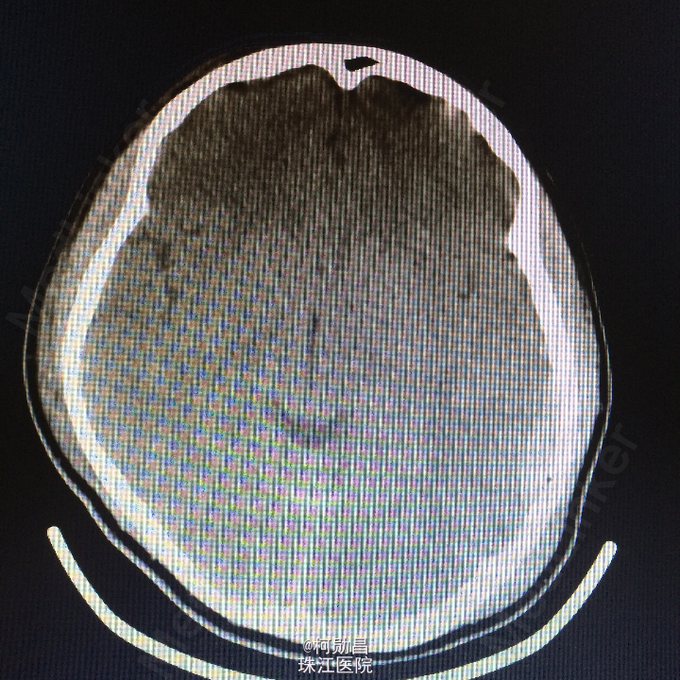

主诉:颅骨损伤后头痛、头晕2天 病史:患者于2天前骑摩托车时与机动车相撞,跌伤头部,至口角、眉弓处多处裂伤出血,左侧外耳道流血,当时患者无意识不清、肢体抽搐等。随即呼叫120送至医院。行头颅CT查示:左顶部硬膜下血肿,蛛网膜下腔出血,予相应治疗后病情稳定 。

查体:脑膜刺激征阳性 辅助检查:复查头颅CT及三维颅骨重建提示:血肿较前吸收,颅骨多发骨折,左额部较为明显

诊断:重型颅脑损伤,脑脊液耳漏、颅骨多发骨折